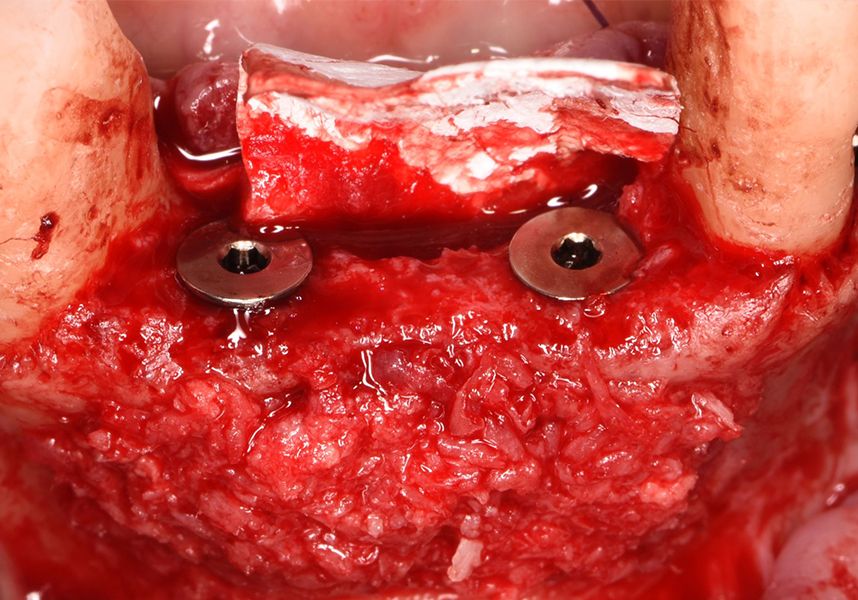

Respecting the three-dimensionally correct position of the implant led to bone fenestration, leaving the apical part of the apex of the implant exposed almost to the mid-point of its length at 42 and a third in 32.

To treat the defect, bone regeneration was carried out simultaneous to the surgical process, with an autologous bone graft from the patient. In the internal part of the graft we used autologous cortical bone obtained by scraping (Safescraper) and from the biological drilling, at low revolutions and without irrigation, from the other implant beds. In the external layer of the regeneration we used a xenograft (Genoss, Osteogenos) and this was covered with a reabsorbable collagen barrier membrane (Evolution STD, Osteogenos).

The membrane was sutured with PGA reabsorbable suture to the periosteum to secure it, thus avoiding subsequent reentry to remove fixings such as tacks.